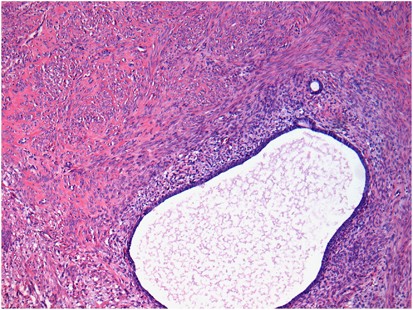

A histological diagnosis of carcinosarcoma depends on identifying high-grade malignant epithelial and mesenchymal components typically showing a sharp demarcation between both, although occasionally this demarcation may be blurred (Figure 1). The epithelial element may include serous, grade 3 endometrioid, clear cell and undifferentiated carcinoma in order of frequency. Admixtures may be seen and typing of the epithelial component may be difficult; in some cases, a hybrid morphology (with features of serous and endometrioid carcinoma) or a malignant squamous component is present (Figure 2), which may be a clue to the diagnosis. The mesenchymal component can be homologous or heterologous. The former is typically a high-grade sarcoma, NOS and eosinophilic hyaline globules are frequently noted. If heterologous elements are present, then rhabdomyoblasts or malignant cartilage is the most common. Osteosarcomatous and liposarcomatous differentiation may rarely occur (Figure 3). On occasion, carcinosarcomas are associated with a component of primitive neuroectodermal tumour (PNET); in such cases, markers such as neurofilament, glial fibrillary acidic protein (GFAP) and synaptophysin may be useful in highlighting this component, which is more analogous to a central than a peripheral PNET without EWSR1 gene rearrangement.9 Occasional examples of a yolk sac tumour component and melanocytic differentiation have also been reported.10, 11

The relative proportions of epithelial and mesenchymal components vary widely; thus, extensive sampling in an undifferentiated sarcoma or pleomorphic rhabdomyosarcoma may reveal areas diagnostic of carcinosarcoma. Uncommonly, carcinosarcomas have a low-power growth pattern, which mimics an adenosarcoma (Figure 4); however, this is usually a focal finding, there is no stromal condensation, and the epithelium and the stroma are overtly malignant at high-power magnification.